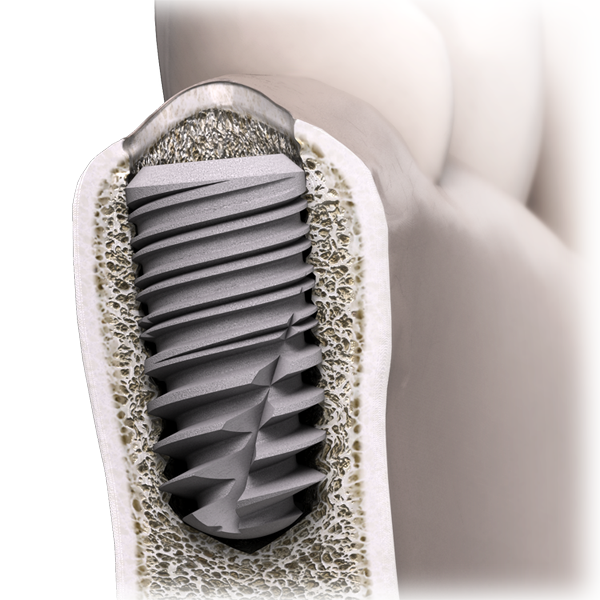

L’implant In-Kone® est un implant type Bone Level.

Sur le plan biologique, le positionnement de l’épaulement de l’implant a été revisité de façon à ce que le chanfrein rugueux puisse se situer sous l’os cortical. L’objectif de ce positionnement est de décharger la crête osseuse de toute contrainte et de recréer un environnement favorable au sertissage de l’implant(1).

Car ce sont les tables osseuses péri-implantaires qui soutiennent la muqueuse et contribuent au rendu esthétique des restaurations.